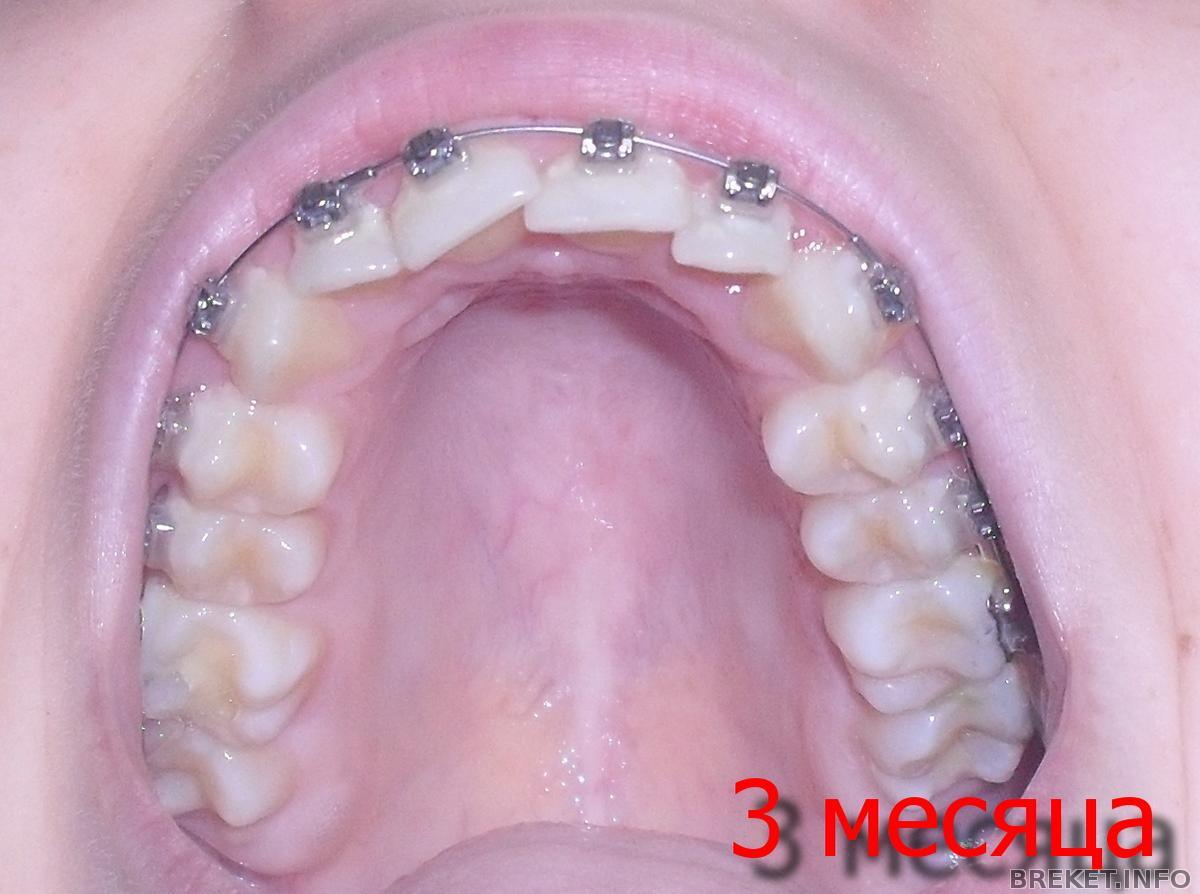

После месяца ношения брекетов:

1.Зубы не болели вообще,как я не ждала.

2. Зубы пожелтели, как я не чистила в течение 5 первых минут после еды.

3. На клыках появились белые пятна.

4. Как была кривая моя двойка справа так и осталась.

5. Поменяли дугу на 4,2. Ощущения натяжения опять нет. Через полтора месяца следующий прием.

фотки прикрепила. Первая дуга по виду была тоньше.

У кого была похожая ситуация? Может не просто дугу надо менять, а еще чем зуб вывернуть в правильное направление? Читать далее »